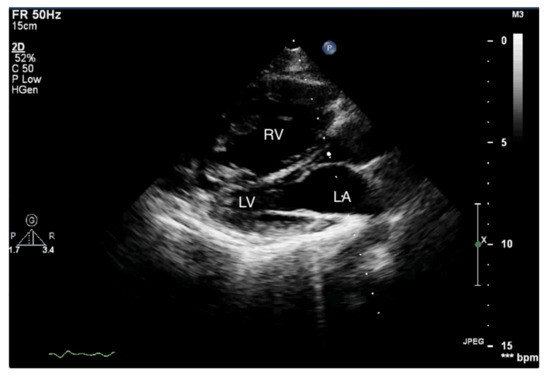

Figure 2.

Enlarged right ventricle. 2D-TTE, parasternal short-axis view (PSAX). RV: right ventricle, LV: left ventricle.